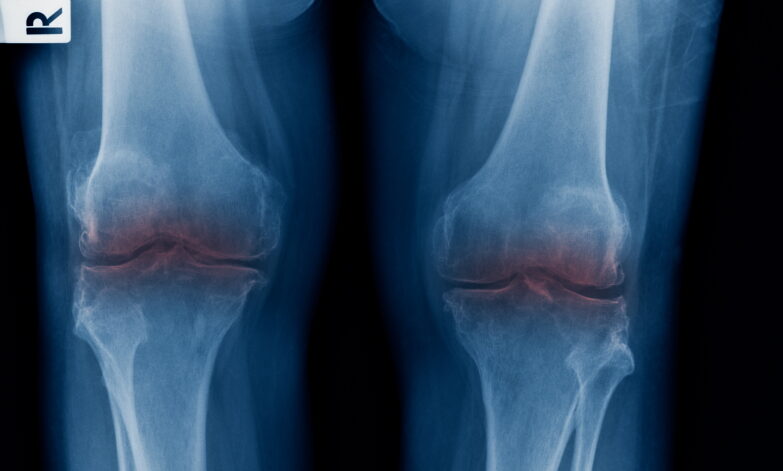

Cartilage-related conditions in the knee can significantly affect joint function and overall mobility. Cartilage is a smooth, flexible tissue that covers the ends of bones within the knee joint, helping to absorb shock and facilitate smooth movement. Damage to the cartilage, whether from injury, overuse, or degeneration, can lead to pain, stiffness, and reduced knee function. Understanding the causes, symptoms, and treatment options for cartilage-related conditions may help individuals manage their symptoms and preserve knee health.

• Cartilage Degeneration: Gradual wear and tear of the cartilage, commonly linked to ageing or osteoarthritis.